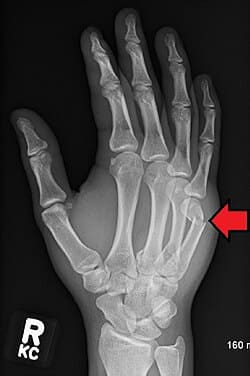

If you’re ready to explore how reconstructive surgery can change your life, now is the time to act. The longer you wait, the more you miss out on living fully. By scheduling a consultation, you’ll take the first step toward restoring your function and confidence. We take care of both hand fractures and wrist fractures, and can get live X-rays in the office to better understand and plan further care.